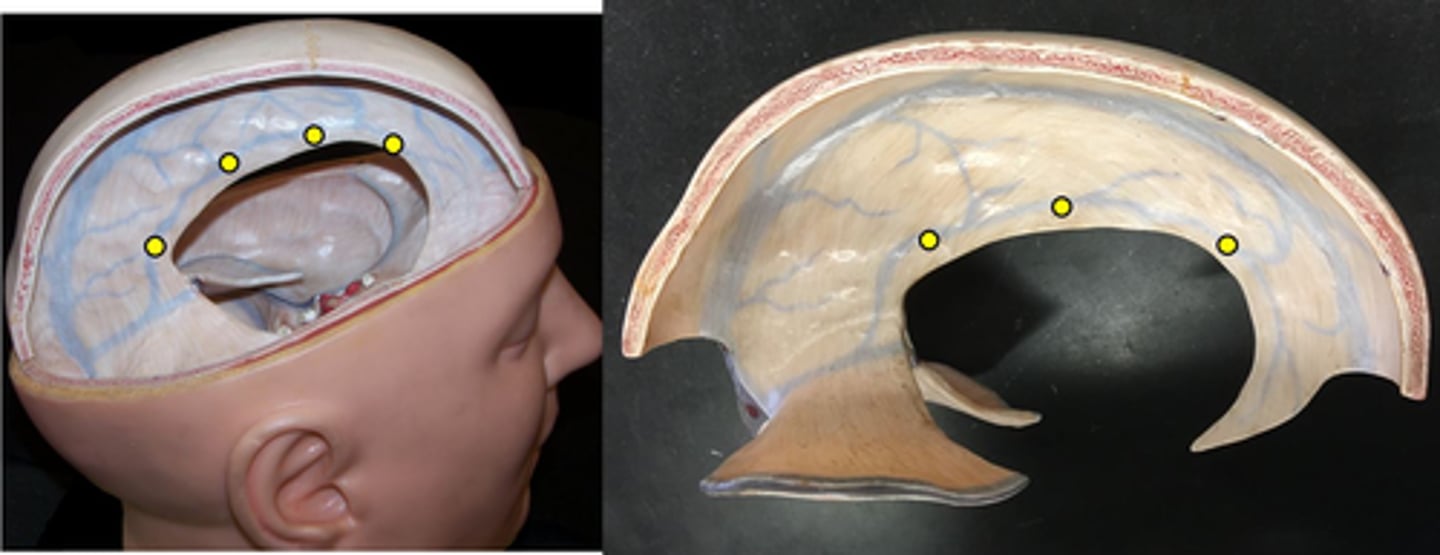

Dura mater

Number 3 on picture

Arachnoid mater

Number 2 on picture

Pia mater

Number 1 on picture

Falx cerebri

separates the two cerebral hemispheres

Tentorium cerebelli

separates cerebrum from cerebellum

Falx cerebelli

separates the two hemispheres of the cerebellum

Superior sagittal sinus

Inferior sagittal sinus

Transverse sinus